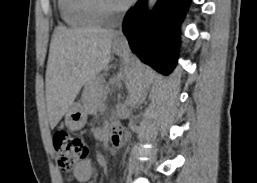

Печеночная ткань имеет обильное кровоснабжение, поэтому часто ультразвуковая диагностика заболеваний печени затруднена. Одним из наиболее информативных методов диагностики является мультиспиральная КТ печени, которая может проводиться в стандартном режиме и с внутривенным болюсным контрастированием. Введение йодсодержащего контрастного вещества значительно повышает диагностическую ценность компьютерной томографии и позволяет, в частности, выявить злокачественное образование на ранней стадии, отличить доброкачественный процесс от злокачественного, визуализировать изменения внутрипеченочных желчных протоков и многие другие патологические процессы.

В нашей клинике сканирование печени выполняется на современном 128-срезовом томографе экспертного класса TOSHIBA AQUILION CXL, который производит послойное сканирование исследуемого органа с последующей цифровой обработкой полученных данных для создания трехмерных изображений печени высокого качества и контрастности. Увеличенное количество детекторов, вмонтированных в аппарат, обеспечивает быстрое время исследования и пониженные дозы рентгеновского излучения, получаемого пациентом.

Мультиспиральная компьютерная томография является быстрым высокоточным и доступным методом исследования, позволяющим обнаружить тяжелые заболевания на ранних стадиях, поставить точный и достоверный диагноз и назначить своевременное лечение.